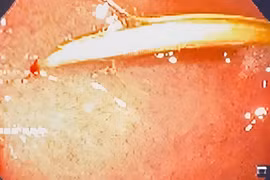

Nhiều loại dị vật có thể đi vào đường tiêu hóa (GI) một cách vô tình hoặc cố ý. Nhiều dị vật tự đi qua ống tiêu hóa, nhưng một số bị dừng lại, gây nên các triệu chứng và đôi khi gây các biến chứng.

(khoahocdoisong.vn) - Cơ thể vẫn khỏe mạnh, không bị đau bụng, vẫn chơi thể thao, nhờ kiểm tra sức khỏe định kỳ, các bác sĩ đã kịp thời tìm thấy dị vật nằm trong ruột của bệnh nhân đồng thời phát hiện sớm viêm ruột thừa.